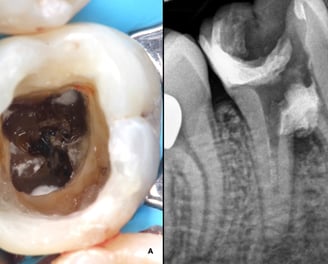

Es un procedimiento en el que se abre la cámara pulpar del diente para eliminar el tejido pulpar infectado o inflamado. Esto ayuda a aliviar el dolor y preparar el diente para un tratamiento de conducto.

Trepanación Pulpar (urgencia)

Es el procedimiento para limpiar, desinfectar y sellar los conductos internos del diente cuando la pulpa está infectada o inflamada. Es esencial para salvar el diente.

Tratamiento de Conducto

Tratamiento de calcificaciones radiculares

Uso de microscopio en endodoncia